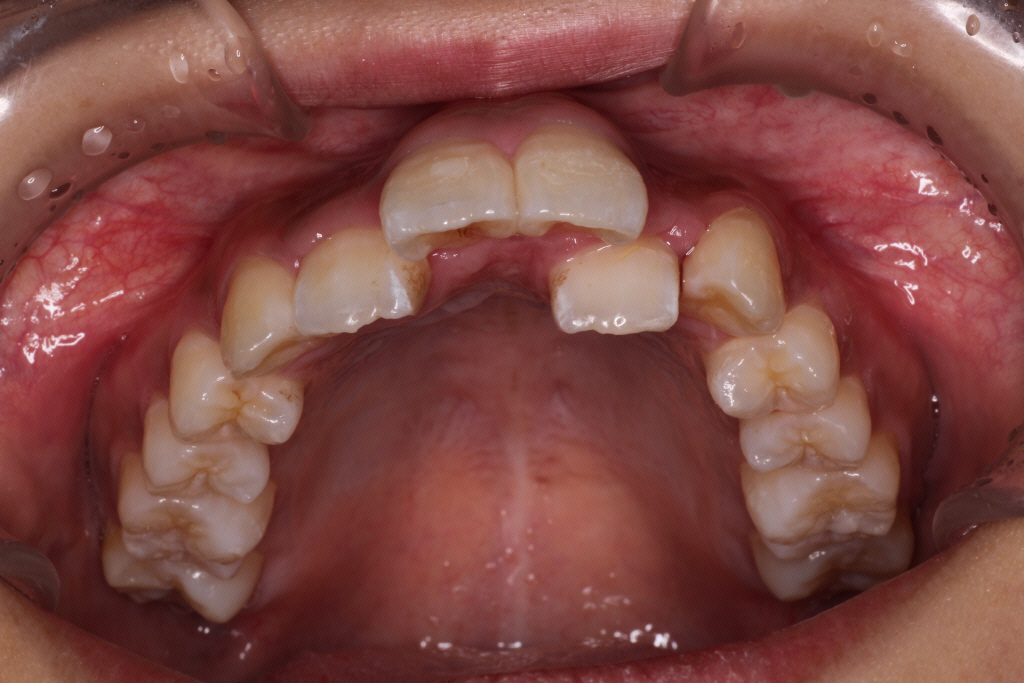

初診時のお口の中の状態です。

上の前から2番目の歯が下の歯列より内側にあり叢生です。

側方の上下の咬合関係が理想の上1本に対して下2本の理想的な噛み合わせではない。

歯列の幅がせまい。

診断:上顎前突・前歯部叢生